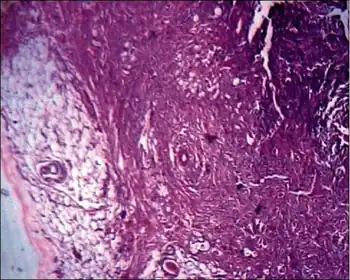

Spindle cell lipoma is an asymptomatic, slow-growing subcutaneous tumor that has a predilection for the posterior back, neck, and shoulders of older men.[1]: 625 [2]